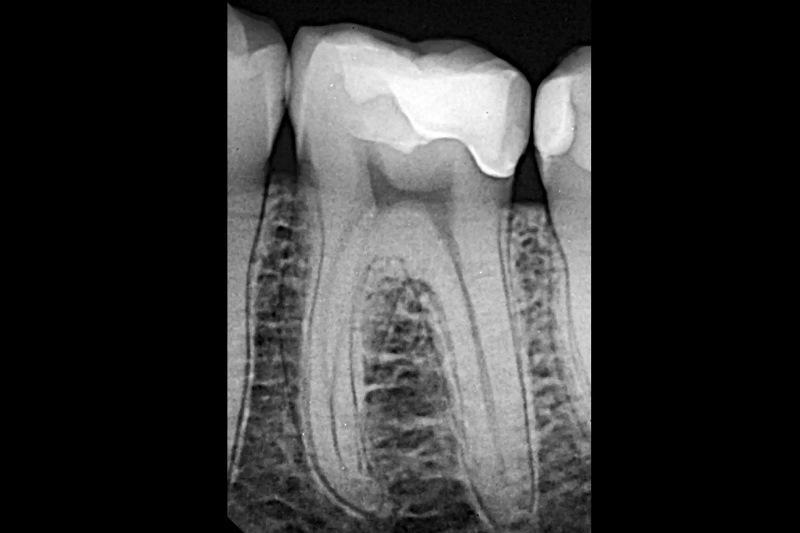

Лечение было сосредоточено на первом моляре нижней челюсти с использованием существующих композитных реставраций I и V классов (фото 1). Состояние зуба протекало бессимптомно, и фриз-тест показал нормальную реакцию. Дистальное кариозное поражение, которое не было клинически заметно, было впервые заподозрено во время планового обследования, и его протяженность была четко определена на панорамной рентгенограмме (фото 2).

Фото 2: Панорамная рентгенограмма, показывающая дистальное кариозное поражение.